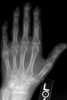

Degenerative arthritis

Osteoarthritis (OA) is a type of joint disease that results from breakdown of joint cartilage and underlying bone. The most common symptoms are joint pain and stiffness. [Source: Wikipedia ]